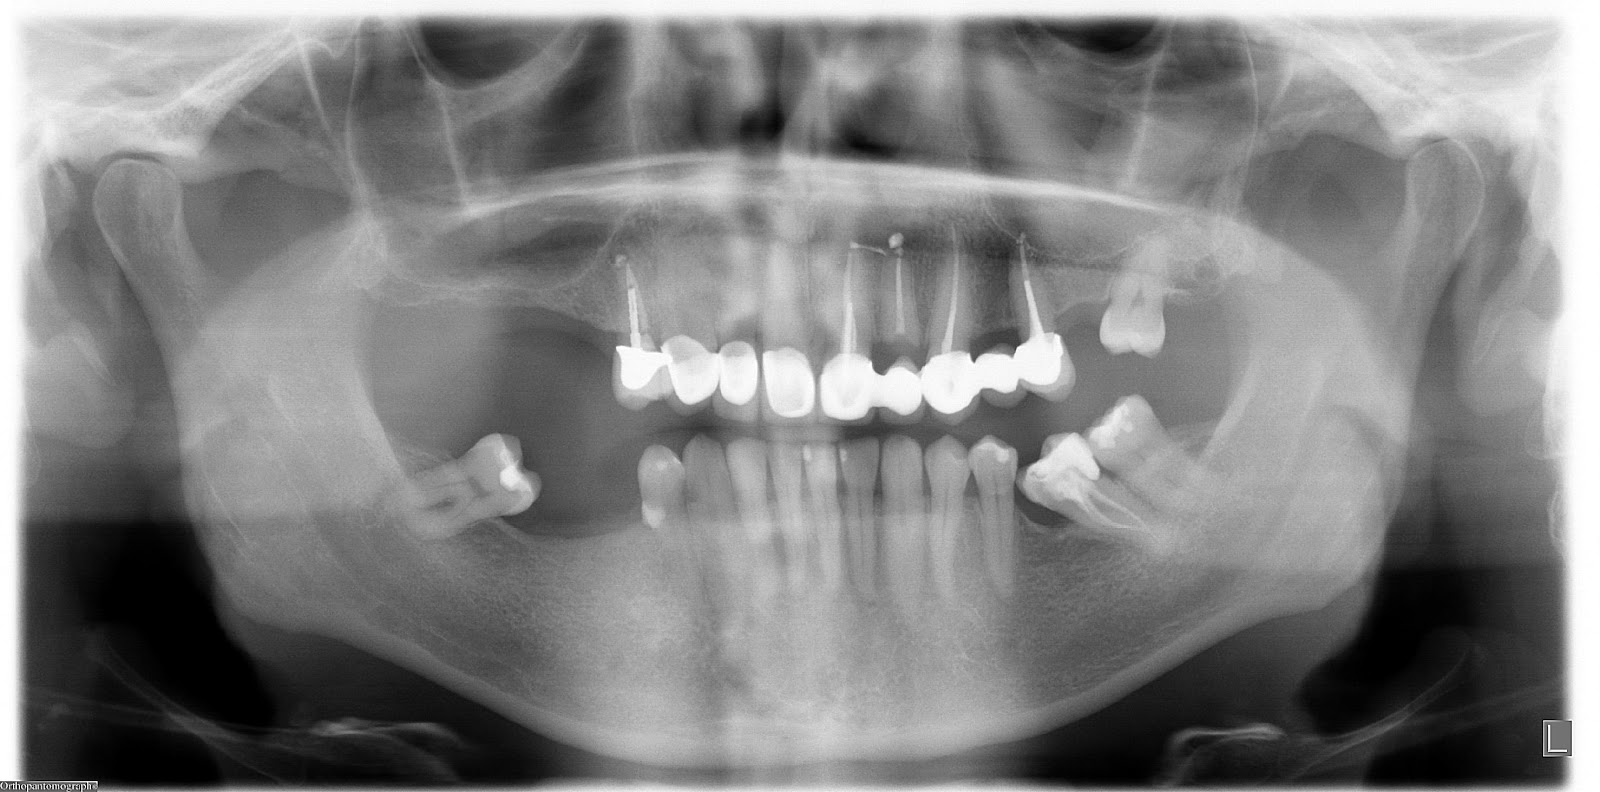

Dental X-rays are more than just tools for diagnosing cavities; they provide a comprehensive view of your oral health status. By allowing dentists to detect problems before they become severe, these images can save patients time, money, and discomfort in the long run. Early detection through modern imaging technology can reveal hidden decay between teeth, bone loss due to gum disease, or even cysts and tumors that are not visible during a standard exam.

- Impacted Teeth - Revealing teeth that are not properly erupting, such as wisdom teeth.

Beyond diagnosis, regular imaging plays a vital role in treatment planning. Whether you're considering braces or implants or undergoing root canal therapy, precise images enable personalized care tailored to your unique anatomy.

Despite the myths surrounding dental x-rays, they play an integral role in preventative dentistry. X-rays allow dentists to detect issues that are not visible during a standard oral exam. This includes early signs of decay between teeth, problems below the gum line, and changes in bone density that could indicate periodontal disease. By identifying these problems early, fundamental dental treatments can be administered promptly, saving patients from more extensive and costly procedures down the line.

Dental x-rays also serve as a critical tool in planning complex dental treatments such as orthodontics, implants, and extractions. The detailed imagery helps create precise treatment plans tailored to each patient's unique anatomy. To explore how modern technology is shaping these plans, visit our page on digital dentistry benefits.